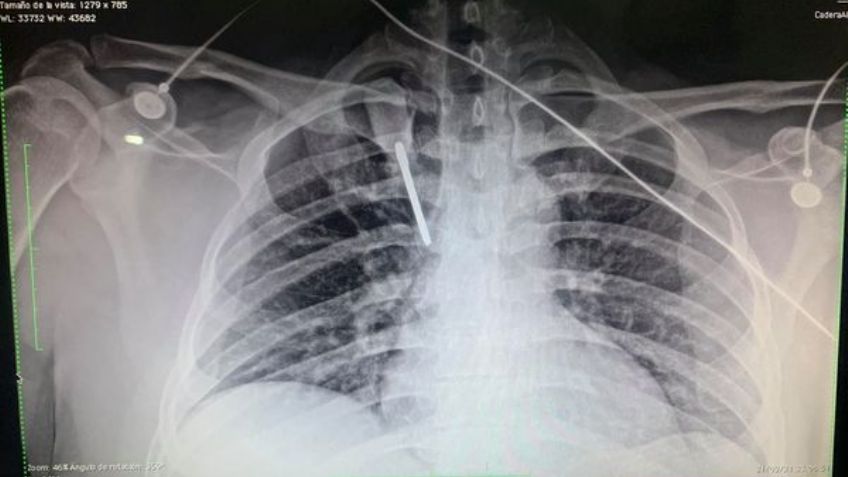

Junto a la publicación, compartió unas fuertes fotografías en las que se ven los rayos equis que muestran la herramienta usada como arma y a él, quien estuvo en un estado de salud crítico.